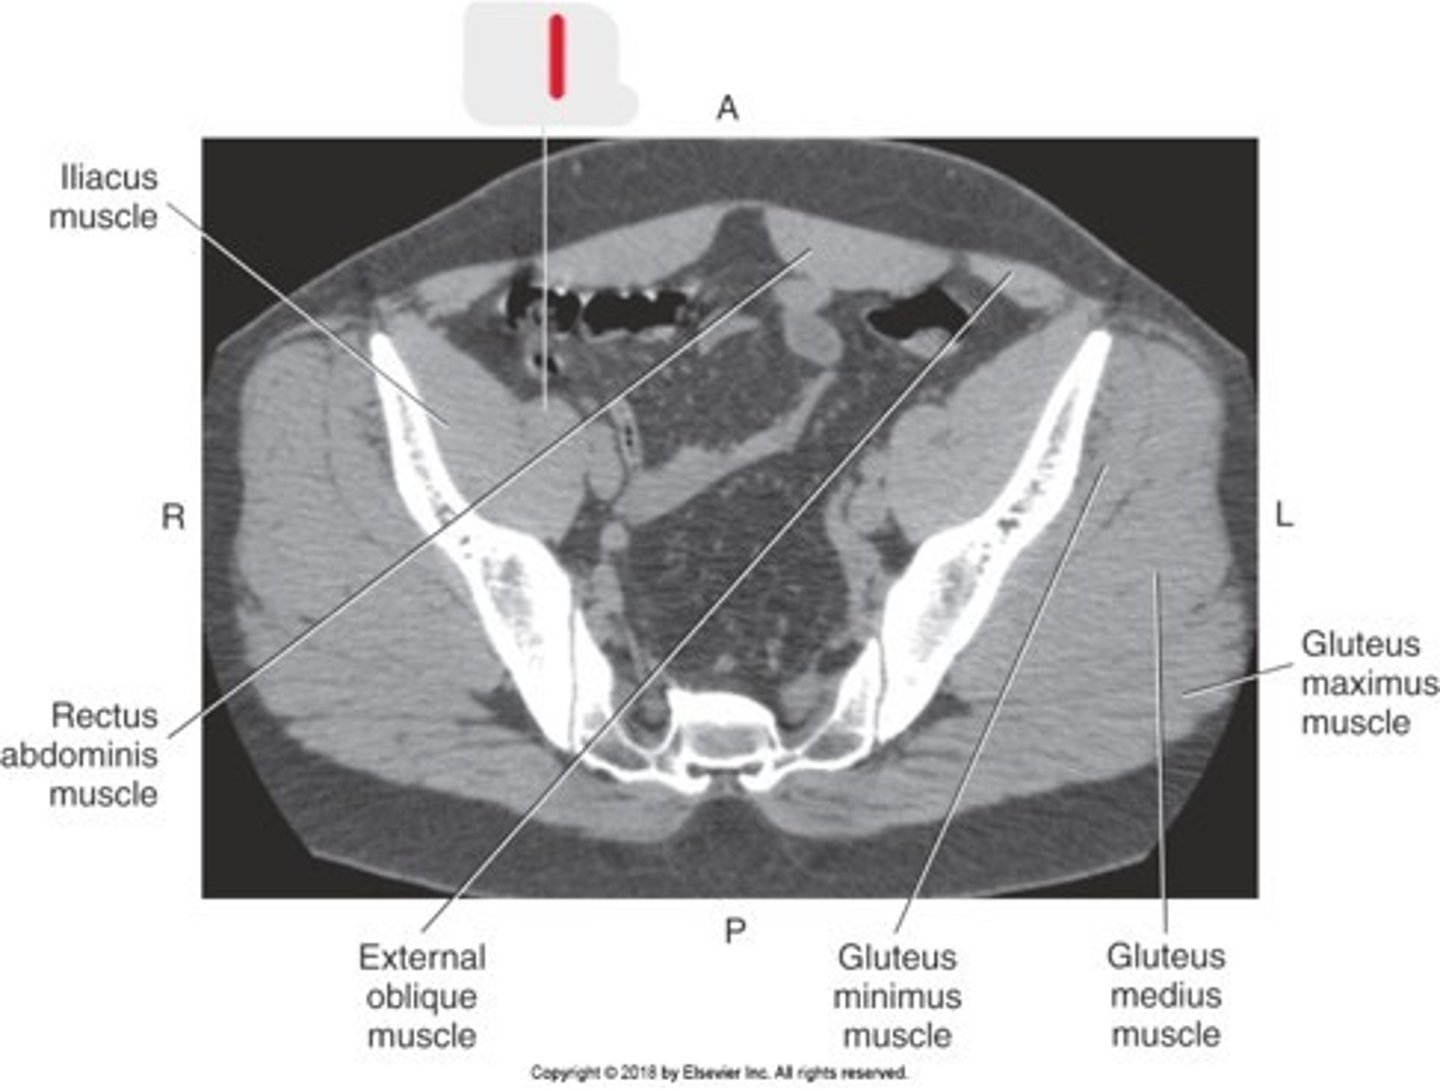

Name all numbered structures

Spinous processes

What structures are these lines pointing to

Blue line- vertebral bodies

Red line- spinal canal

What is the blue line pointing to and what is the red line pointing to

What are the blue lines pointing to

Psoas muscles

Name #2 on this image

Lumbar spine because of the disc space

What type of vertebrae is this and how can you tell

Ilium

Name #1

Psoas major muscle

Name the numbered structure

Psoas muscles

What are the blue lines pointing to